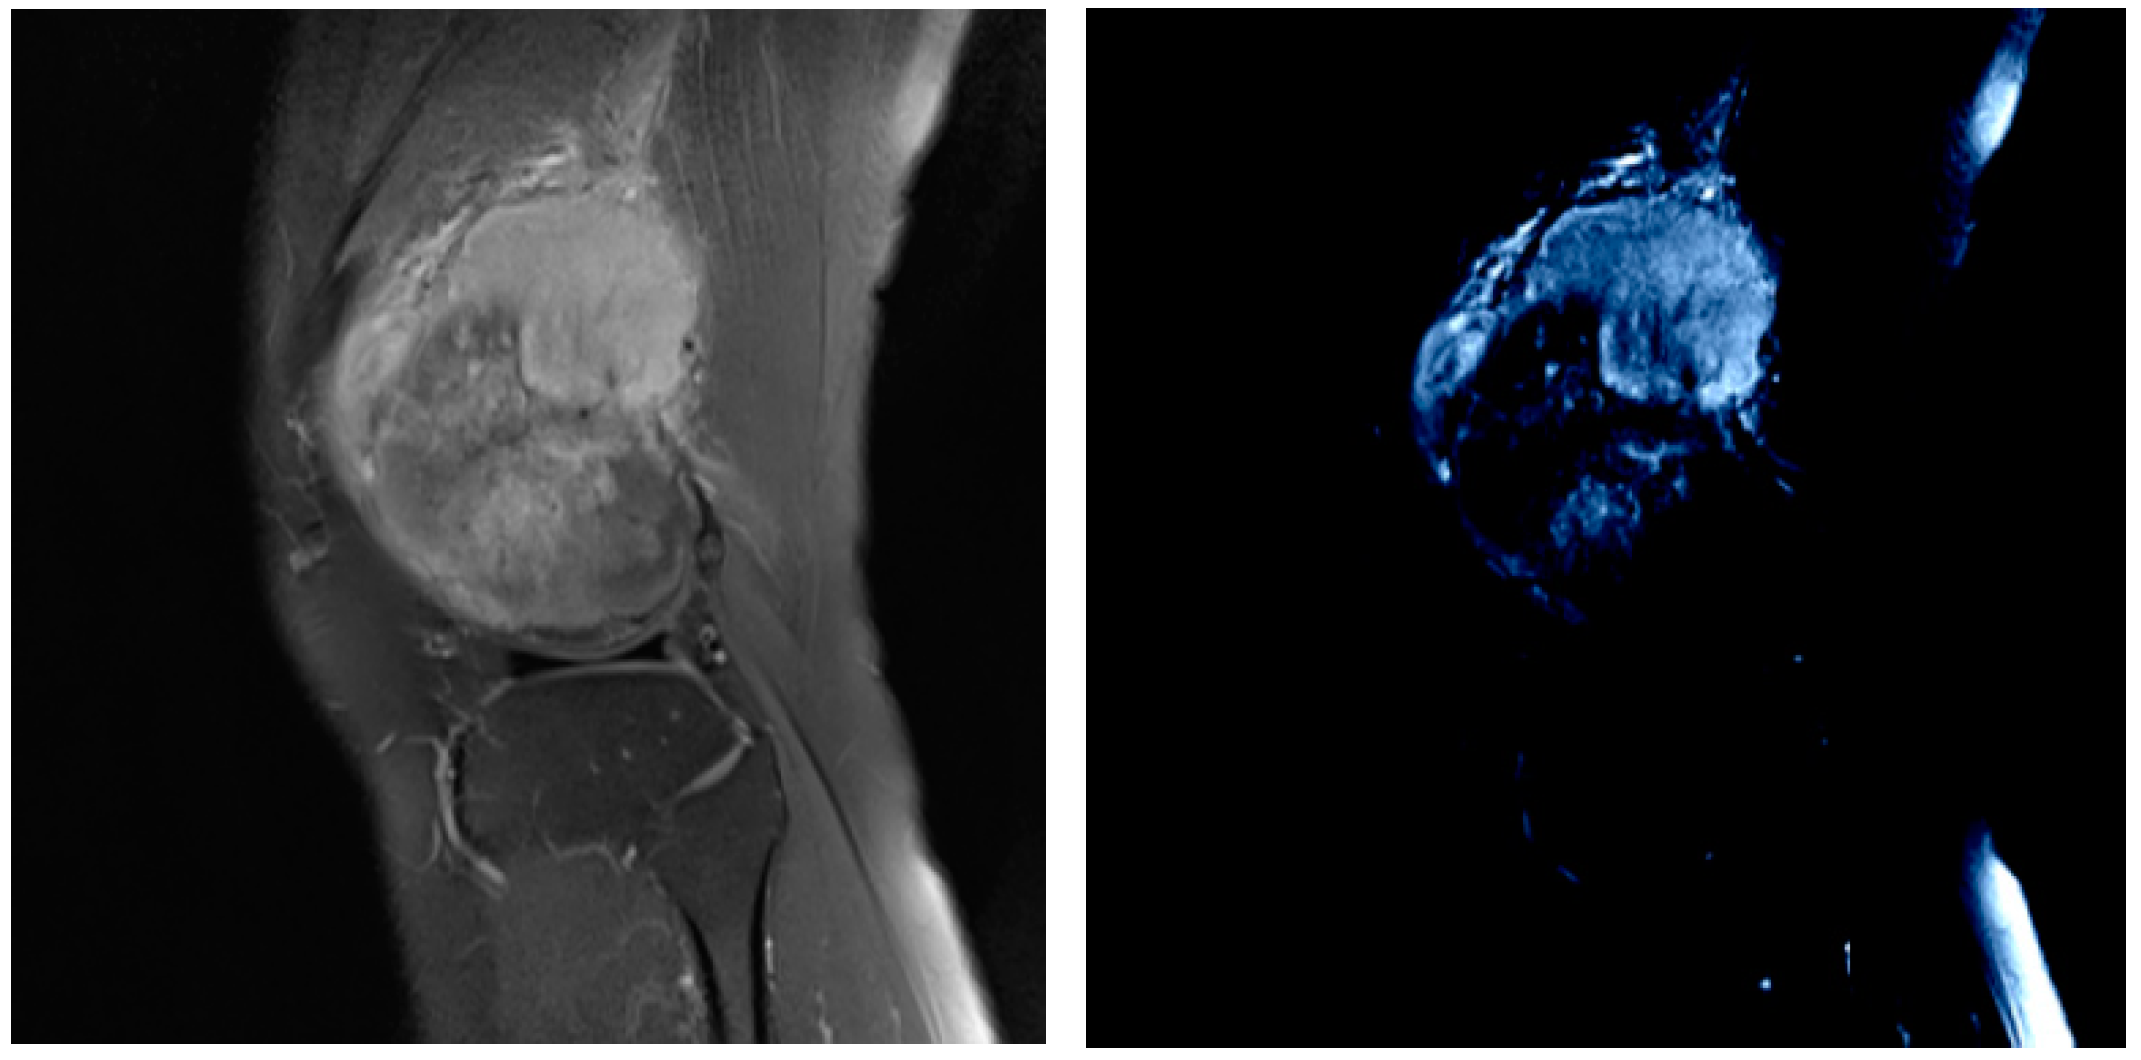

Multi-Scale Tumor Localization Based on Priori Guidance-Based Segmentation Method for Osteosarcoma MRI Images

- This paper proposed a prior-guided-based MRI image segmentation method for osteosarcoma (PESNet), which adds a priori generation and feature enrichment network to effectively improve the localization accuracy and segmentation accuracy of multi-scale tumors.

- The datasets used in this experiment were all from more than 200 real samples from the Second Xiangya Hospital. The results showed that the proposed segmentation method outperforms other methods. The prediction results of the model can be used as an auxiliary basis for doctors’ clinical diagnoses and improve the accuracy of diagnosis.

- Prior Generation. In contrast to the adverse effects of high-level features on the performance of few-shot segmentation, prior segmentation frameworks use these features to provide semantic cues for the final prediction. We performed prior generation processing on MRI images of osteosarcoma to reduce the interference of invalid active segmentation regions on the final prediction, thereby improving the efficiency of image processing.

- Pretreatment. We further preprocessed the MRI image generated after prior generation, and processed the mask and prior generation results respectively by deleting isolated highlights and the normalization algorithm to speed up model training and save computing resources.

- Image analysis and segmentation. The segmentation model in this paper is a feature enrichment network based on prior guidance. When training the model, the MRI image of osteosarcoma and its preprocessed mask were input into the network to confirm loss function, and the error segmentation rate of the osteosarcoma image was reduced through repeated training.